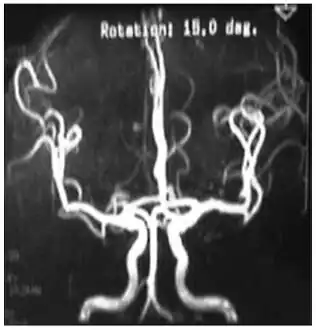

Cerebral vessels by brain MRA show cerebral atherosclerosis (and minor angiostenosis)

Angio MRI of supra-aortic vessels after the injection of 20cc of gadolinium for contrast